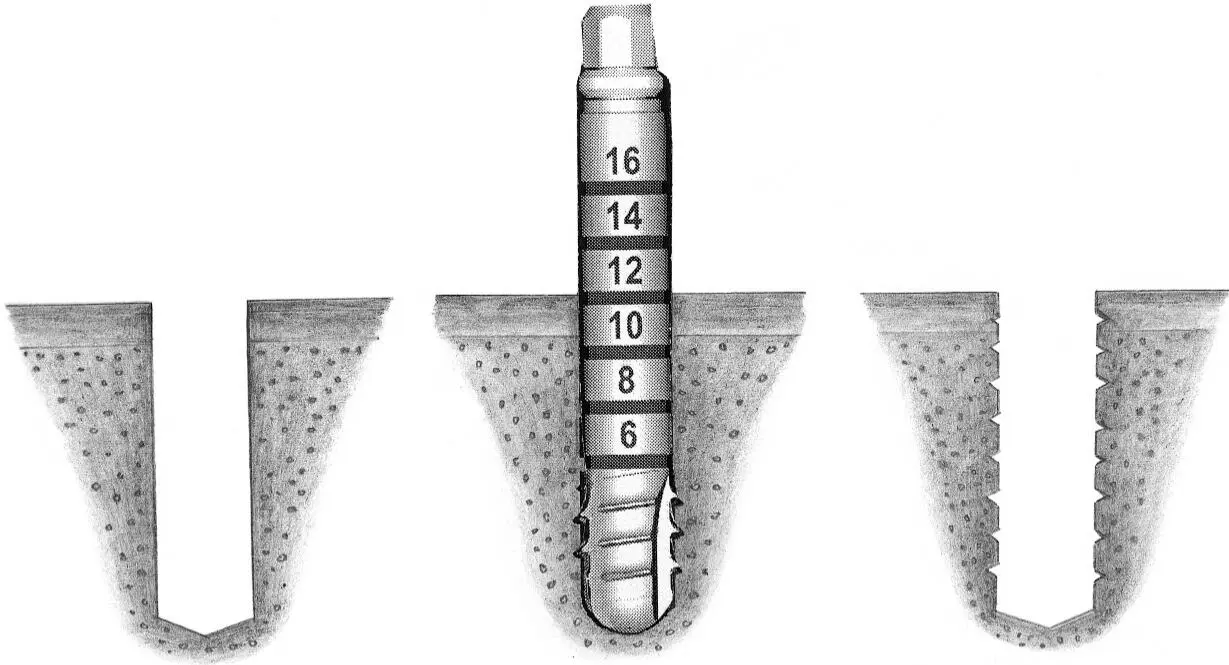

Fig 1-2Sequence of site preparation for a standard implant.

Fig 1-2a A no. 1 round bur is used to mark the position of the implant site.

Fig 1-2b Access is widened with a no. 2 round bur. This step makes it possible to correctly position the next drill.

Fig 1-2c The initial implant site preparation is made with a 2.2-mm-diameter pilot drill.

Fig 1-2d A 2.2-mm-diameter guide pin is inserted into the initial preparation to check its position and axis.

Fig 1-2e The crest of the osteotomy is enlarged with a no. 3 round bur.

Fig 1-2f A 2.8-mm-diameter spiral drill is easily inserted for preparing the depth of the site.

Fig 1-2g A profile drill is used to further increase the surgical access for the next, larger-size drill.

Fig 1-2h Preparation of the implant site continues with the 3.5-mm-diameter spiral drill.

Fig 1-2i Occasionally, when the bone structure is uniformly dense, bone tapping is performed prior to implant placement.

Fig 1-2j A standard implant is placed in the site, with the rough surface positioned at the level of the alveolar ridge crest. This allows the implant shoulder to be located at the gingival level.